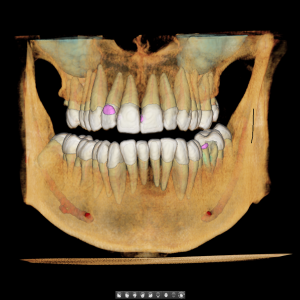

Digitalni telerendgen omogućava ortodontu da proceni:

1. međusobni odnos vilica

2. položaj i nagib zuba

3. skeletni tip pacijenta

4. pravac rasta vilice

5. odnos mekih i tvrdih tkiva.